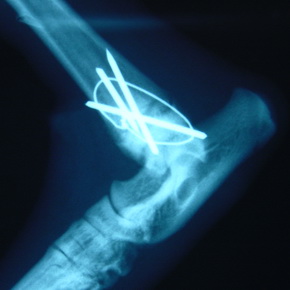

Orthopädie / Gelenkoperationen / Kreuzbandriß

Chirurgie / Bauch- und Brustkorboperationen